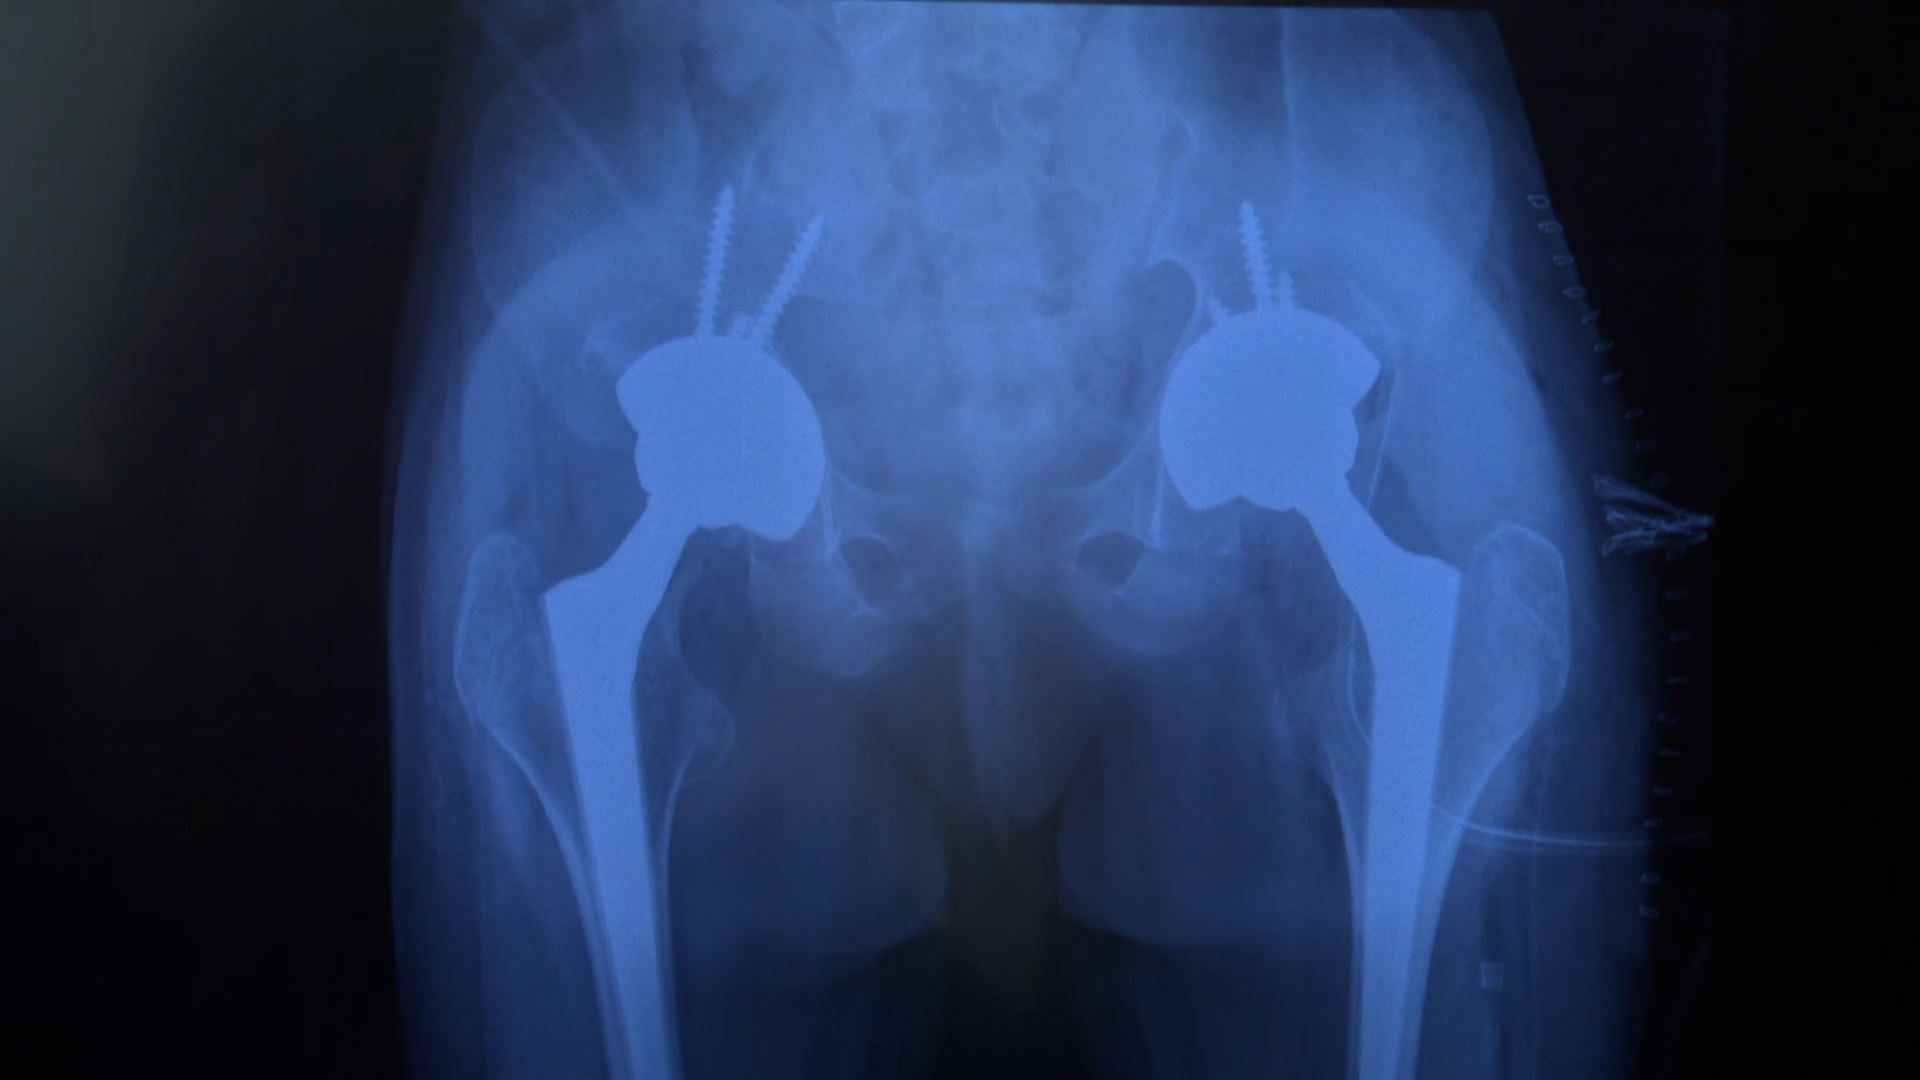

Уникальную операцию, 12-летней пациентке провели специалисты НМИЦ имени Г. И. Турнера. Врачи выполнили ребёнку двустороннее эндопротезирование тазобедренных суставов.

У девочки с рождения редкая форма скелетной дисплазии, из-за которой нарушена плотность костей. Впрочем, это заболевание ей никак не мешало жить. Она прыгала и бегала — как и все дети в ее возрасте. Пока не тот случай в школе. Оказалось, что головки обеих бедренных костей оторваны и смещены — проще говоря, это двусторонний перелом шейки бедра, который дети могут получить в результате ДТП или падения с высоты. Девочка не могла выпрямиться и разогнуть колени, поэтому она ходила согнувшись.

Еще чуть-чуть и Жасмин вовсе перестала бы ходить. В родной Караганде врачи не решились на такую сложную операцию. Помочь вызвались специалисты из Центра имени Г. И. Турнера. Хирурги провели двустороннее эндопротезирование тазобедренных суставов — такое вмешательство у детей считается крайне редким. Операция шла в два этапа. При этом врачи впервые решили не ждать положенных полгода — под угрозой оказалась подвижность левой ноги.

«Обычно мы берем на второе протезирование спустя шесть месяцев после первого, дав человеку возможность походить, адаптироваться. Но вторая нога тоже была в контрактуре, она сильно мешала дальнейшей работе первой. Поэтому мы приняли немного нестандартное решение и выполнили вторую операцию через три месяца. Убрав контрактуру в другом суставе, мы смогли добиться в нем нормальной амплитуды движений и доработать второй сустав», — объяснил заведующий отделом заболеваний суставов и костной патологии НМИЦ детской травматологии и ортопедии имени Г. И. Турнера Минздрава РФ Павел Бортулёв.